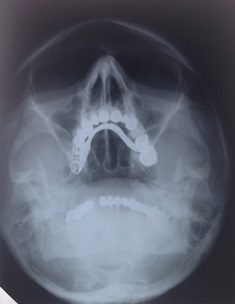

Until the x-ray, all knowledge of human anomalies (apart from visible ones) was limited to those found by anatomists at dissection. But now, new living anatomy was being shown on radiographs.

As this different view of the body came about, the interpretation of shadows had to be made with care. Early radiologists were like aircraft spotters.[ix] Abnormalities of forensic importance were (still are) often subtle and the shadows cast by the new rays could often be confusing. And, of course, what was normal?

By the 1920s, radiology was becoming recognised as a distinct medical speciality. In the 1930s there was a gradual standardisation of projections which culminated in the publication of Positioning in Radiography by Kitty Clark in 1939, which remains in print today.

It was all about the position. We could see if there was something wrong with my head if I put it in the same position as yours.

He writes a book on neuroradiology. How to x-ray the brain. He publishes it twice. By the time the second edition emerges it is already nearly out of date. The CT scan and MRI are developing quickly and so much of his research is obsolete.